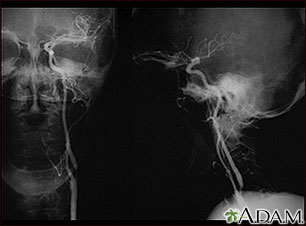

Estenosis carotídea; radiografía de la arteria izquierda

El arteriograma carotídeo es un estudio de rayos X que sirve para determinar si existe una estrechez u otra anomalía en la arteria carótida, que es la arteria principal que va al cerebro. Este es un angiograma de la arteria carótida común izquierda (vista lateral, frontal y anterior) que muestra una estrechez severa (estenosis) de la arteria carótida interna justo más allá de la división de la arteria carótida común hacia las ramas internas y externas.